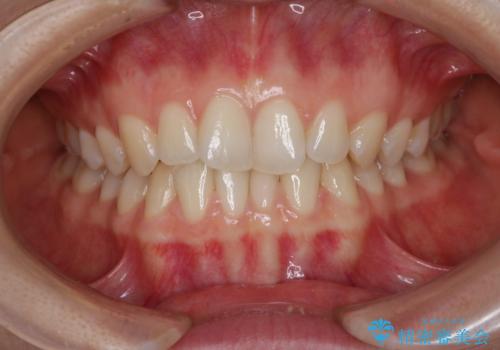

- 上下前歯のがたつきが気になるとご相談にいらした方です。

一見前歯のがたつきだけ改善させれば良い様に見えますが、このがたつきの原因は奥歯の嚙み合わせのズレからくるものであったため、インビザラインFULLで噛み合わせの改善から行っていきました。前歯の角度も改善されたために頑張って唇を閉じる必要がなくなり、横顔のシルエットも綺麗になりました。